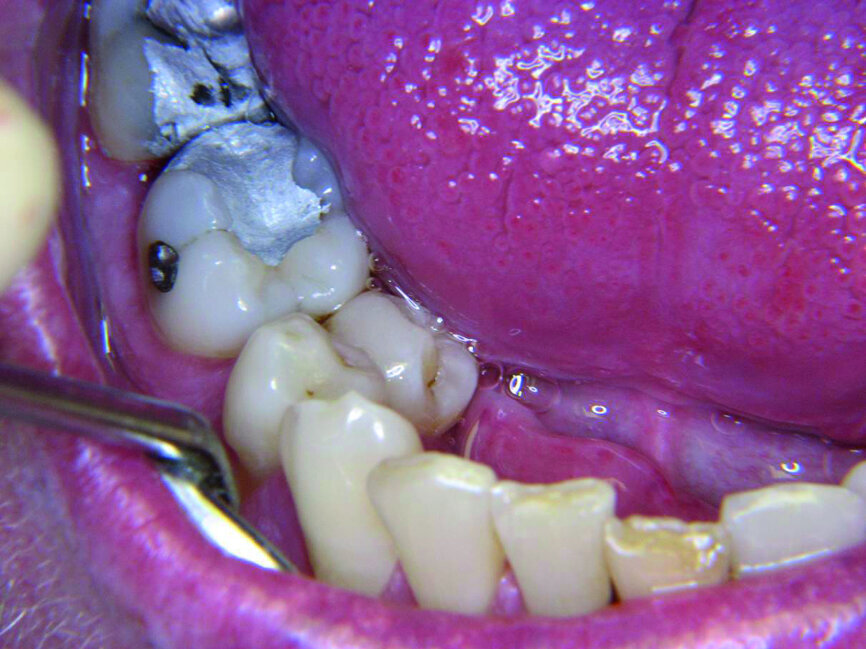

Les premières prémolaires figurent nos aspirations et notre moi, ce que l’on pourrait résumer par les simples mots « moi, je veux » (Fig. 1). La première prémolaire supérieure droite reflète l’image de soi que l’on voudrait montrer aux autres et la gauche celle des désirs affectifs. Les premières prémolaires supérieures comptent parmi les dents les plus fréquemment traitées et font l’objet d’interventions qui vont des obturations au traitement endodontique, à la pose de couronnes et aux extractions (Fig. 2). Cela n’a rien de surprenant si l’on pense aux notions auxquelles nous confrontent les médias au quotidien : quels dehors devons-nous afficher et que devons-nous acheter pour atteindre l’idéal ? Plutôt que de satisfaire nos désirs affectifs profonds, nous sommes astreints à suivre le troupeau.

Les deuxièmes prémolaires peuvent être résumées par les mots « je veux créer » ou « mon moi créatif » (Fig. 3). La deuxième prémolaire supérieure droite symbolise ce que l’on veut développer dans le monde extérieur, nos enfants ou nos hobbies, et la deuxième prémolaire supérieure gauche nos dons naturels. La deuxième prémolaire inférieure droite, similairement à la première prémolaire adjacente, témoigne de notre capacité d’accomplir nos projets, particulièrement dans le domaine du travail. Ainsi, après la restauration d’une anodontie au moyen d’un bridge sur inlay, une jeune patiente dans l’indécision a terminé brillamment ses études au grand bonheur de ses parents (Fig. 4). Par contre les figures 5 et 6 sont des photographies de patients chez qui l’évolution professionnelle se place toujours au second rang des priorités.